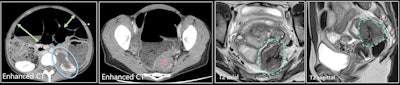

In the acute setting, noninvasive diagnosis of bowel endometriosis can be achieved with CT or MRI. CT provides a positive diagnosis of obstruction and/or perforation. An eccentric noncircumferential nodular thickening of the bowel wall responsible for small or large bowel obstruction on CT in a woman of reproductive age is suggestive of endometriosis.

"It is well known that patients with endometriosis have an inflammatory process within the peritoneal cavity," Mandoul and colleagues explained. "In our case, an acute process of inflammation of the peritoneal implant was responsible for acute right lower quadrant pain, a differential diagnosis for appendicitis, and salpingitis."

The possibility of inflammatory peritoneal endometriosis can be considered in cases of isolated peritoneal fat stranding with a stellar mass in a woman of reproductive age.